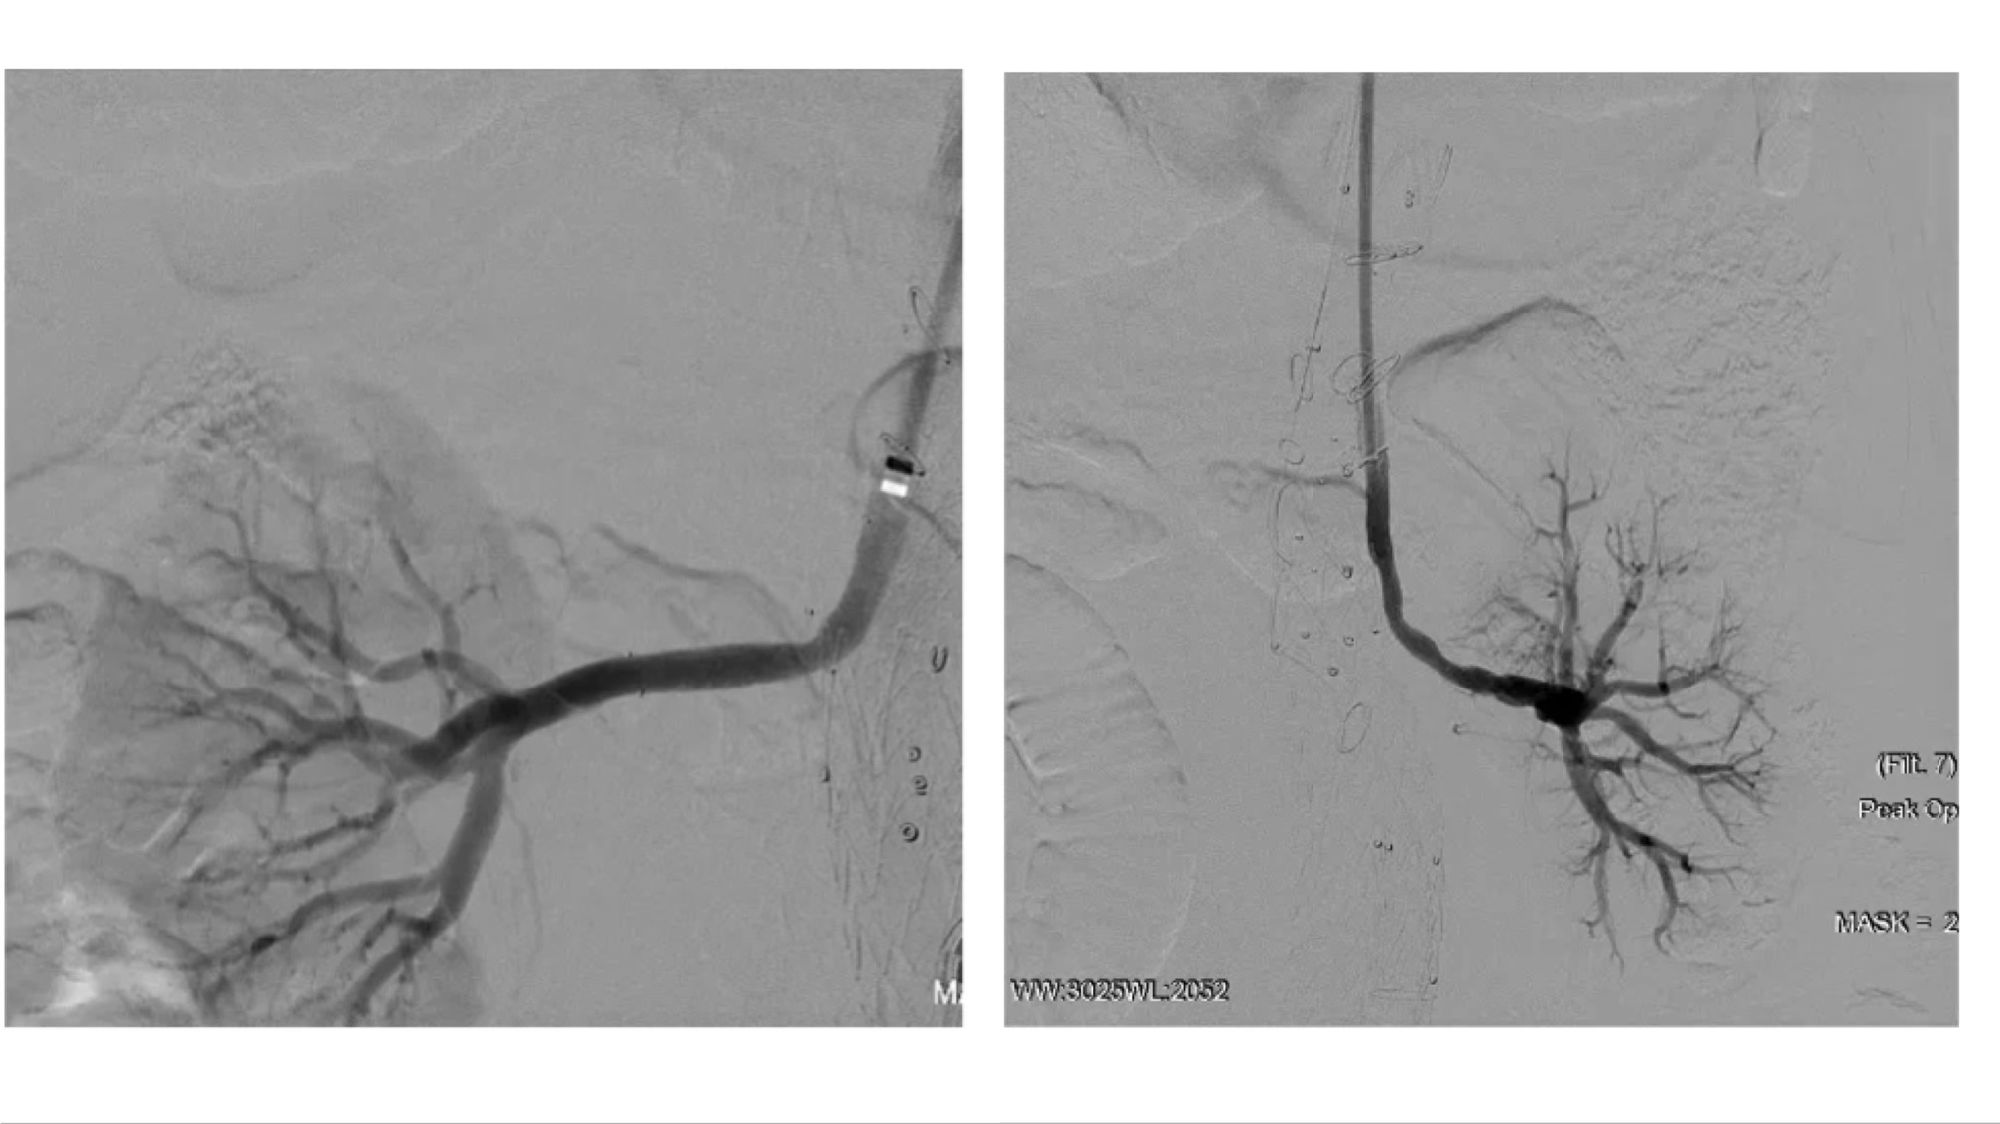

腔内重建腹腔干和肠系膜上动脉

腔内重建右肾和左肾动脉

(右肾开口处重度狭窄,左肾烟囱支架术后增加了手术难度)

术后造影及出院前随访:

患者胸腹主动脉瘤隔绝完全,支架位置及形态良好,各分支动脉重建后血流通畅,无内漏发生。